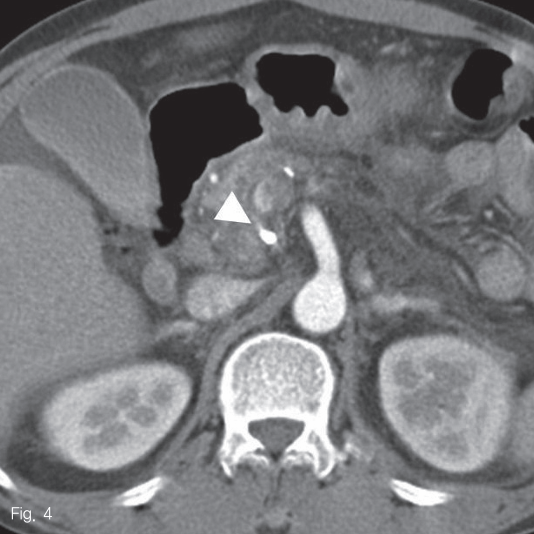

시술 후 혈청 amylase와 lipase 수치가 272U/L와 405U/L로 증가하였다가 3일 후에 정상화되었다. 시술 다음 날 시행한 조영 증강 복부 전산화 단층촬영에서 췌장의 가성동맥류에 glue로 인한 고음영 병변이 있었고 동맥류 내로 잔여 혈류는 보이지 않았다 (Fig. 4).

Fig 4

An axial CT image shows hyperattenuated lesion by glue material within the previous pseudoaneurysmal sac without residual blood flow.